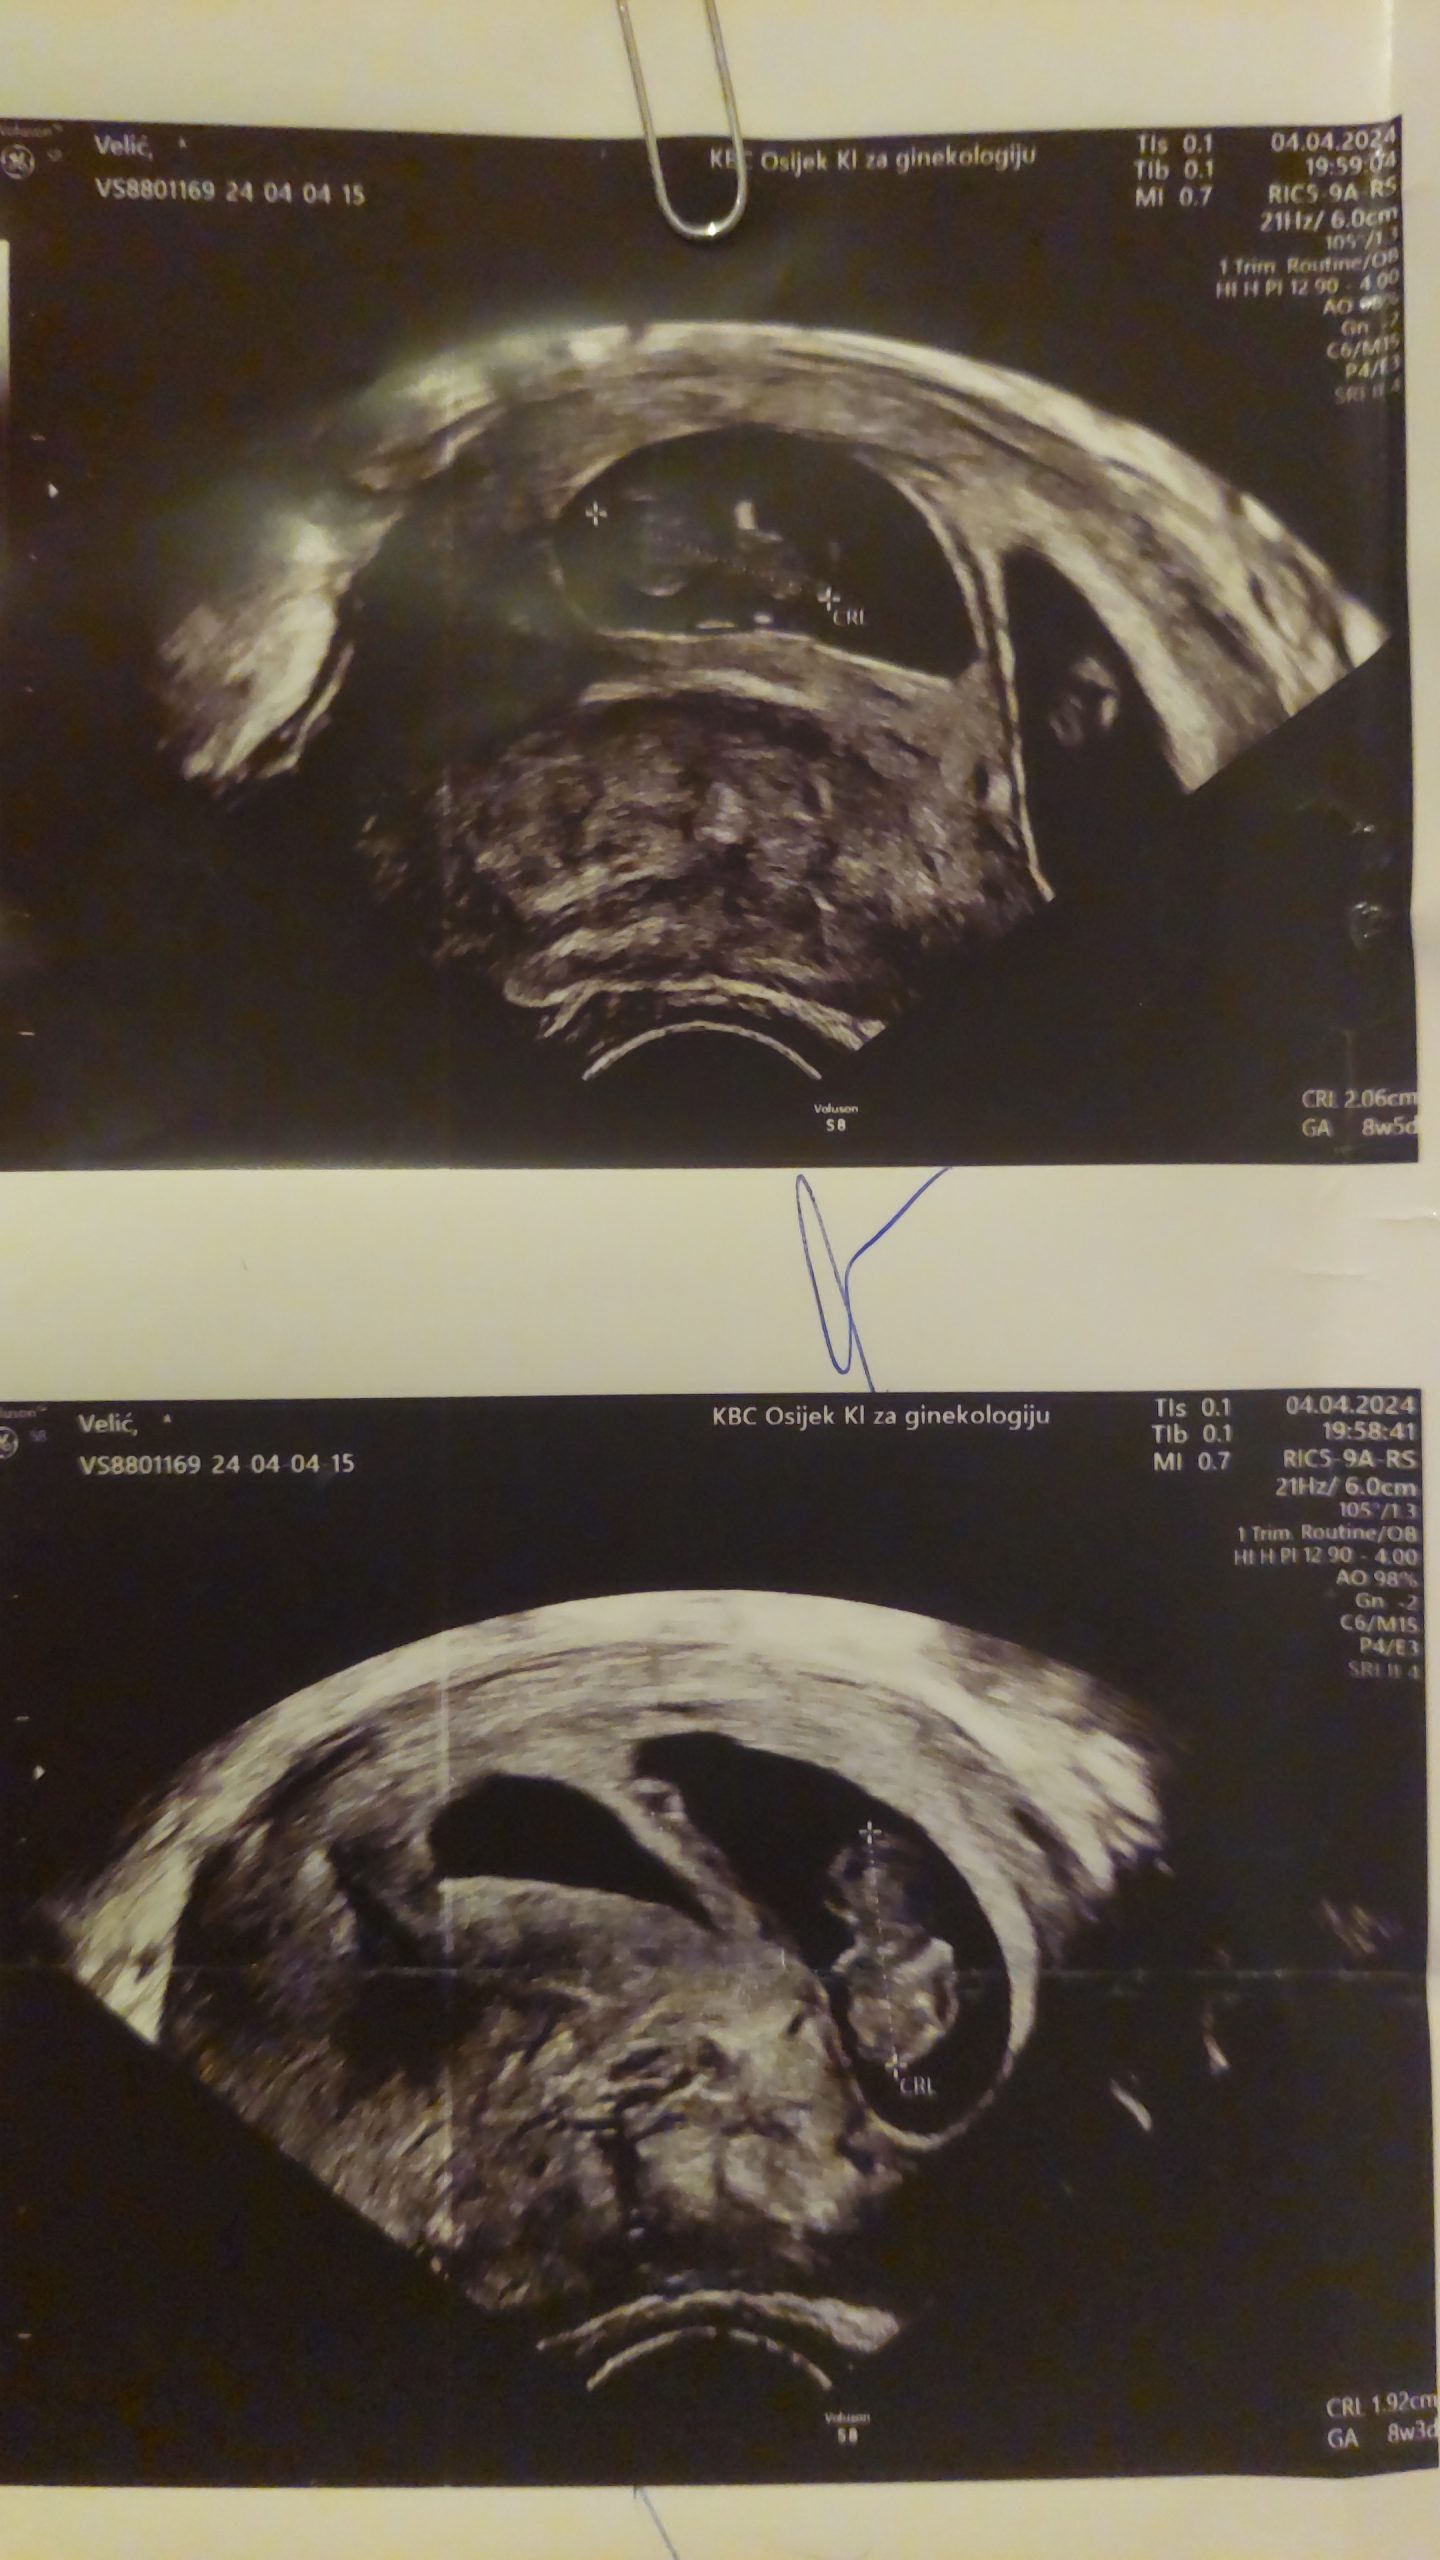

MOJ JUHUUU TRENUTAK JE KAD SAM SAZNALA DA NOSIM BLIZANCE 🥹